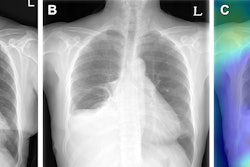

Occlusion maps identifying key features in representative chest x-rays with high and low diagnostic scores. Dark green pixels highlight significant features for model prediction, primarily associated with cardiomediastinal, upper abdominal, lower neck, and supraclavicular regions. Examples of CXRs with high and low diagnostic scores are presented. Image and caption courtesy of Nature Communications through CC BY 4.0.

Occlusion maps identifying key features in representative chest x-rays with high and low diagnostic scores. Dark green pixels highlight significant features for model prediction, primarily associated with cardiomediastinal, upper abdominal, lower neck, and supraclavicular regions. Examples of CXRs with high and low diagnostic scores are presented. Image and caption courtesy of Nature Communications through CC BY 4.0.The prospective test dataset of 9,943 images included 8,382 (84.3%) patients with no type II diabetes, 1,119 (11.3%) who had controlled disease, and 442 (4.4%) with poorly controlled disease. According to the findings, the model effectively detected type II diabetes with an area under the receiver operating curve (AUC) of 0.84 and a 16% prevalence. The model flagged 1,381 cases (14%) as suspicious for type II diabetes.

Finally, the authors noted that the occlusion maps generated to display the basis for the DL model's decisions corresponded significantly to known fat distribution features for the disease in the central chest, lower neck, upper abdomen, and axillary regions.